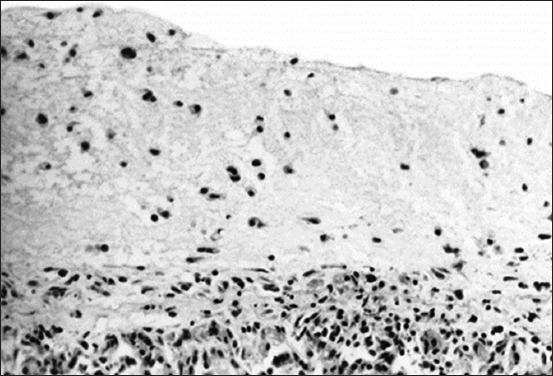

Feline infectious peritonitis (FIP) is an infectious disease characterized by non-specific laboratory changes and clinical signs. Clinical symptoms include anorexia, jaundice, fever, and weight loss. Moreover, some lesions are found in the digestive and respiratory systems. FIP, whose virulence varies, cannot be distinguished using several diagnostic methods. Moreover, feline coronaviruses (FCoVs) can be classified into two serotypes based on differences in their amino acid sequences, spike (S) protein sequences, and antibody (Ab) neutralization. There are two pathotypes, namely those caused by FCoV, which are often referred to as feline enteric coronavirus and FIP virus (FIPV). Furthermore, FIPV infection can be caused by sub-neutralizing levels of anti-FIPV S Abs. Therefore, a supporting diagnosis is needed to confirm FIP because there are no specific symptoms. This review aimed to provide updated information on FIP, including epizootiology, clinical and pathological characteristics, pathogenesis, hematology, clinicopathological and imaging features, pathological features, experimental infection, treatment and prevention, infection and immunity, animal and public health considerations.

猫传染性腹膜炎(FIP)是一种以非特异性实验室变化和临床症状为特征的传染病。临床症状包括厌食、黄疸、发热和体重减轻。此外,在消化系统和呼吸系统中发现了一些病变。FIP的毒力各不相同,无法通过几种诊断方法进行区分。此外,猫冠状病毒(FCoV)可根据其氨基酸序列、刺突(S)蛋白序列和抗体(Ab)中和作用的差异分为两种血清型。有两种致病型,即由FCoV引起的,通常称为猫肠道冠状病毒和FIP病毒(FIPV)。此外,FIPV感染可能由抗FIPV S抗体的亚中和水平引起。因此,由于没有特异性症状,需要进行辅助诊断来确诊FIP。本综述旨在提供有关FIP的最新信息,包括流行病学、临床和病理特征、发病机制、血液学、临床病理和影像学特征、病理特征、实验感染、治疗和预防、感染和免疫、动物和公共卫生考虑因素。